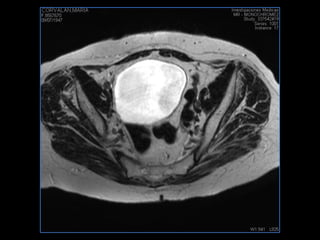

PROTOCOLO pelvis SAG T2, Y FAT SAT (FINOS) AXIAL T1  AX FAT SAT CON   GADOLINIO :  AX T1 Y COR T1 SAT: NO  FASE: RL THK: 3MM  COIL:  GAP: (FACTOR 1.4) 1MM FOV: 40 CM NEX:2 SINCRONIZACION RESPIRATORIA EN 3 O 4 CICLOS ALE